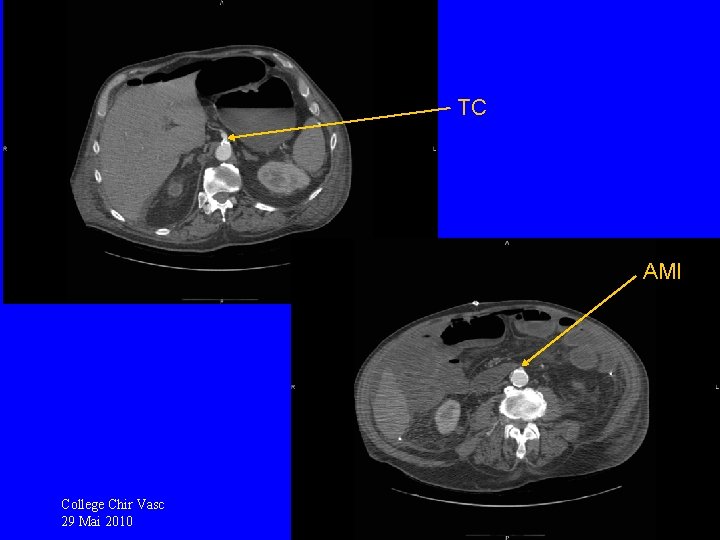

Suites opératoires difficiles Iléostomie productive mais d’aspect ischémique TDM 29/04: sténose très serrée de l’AMS, TC avec plaque, AMI perméable, pas de souffrance intestinale College Chir Vasc 29 Mai 2010

TC AMI College Chir Vasc 29 Mai 2010